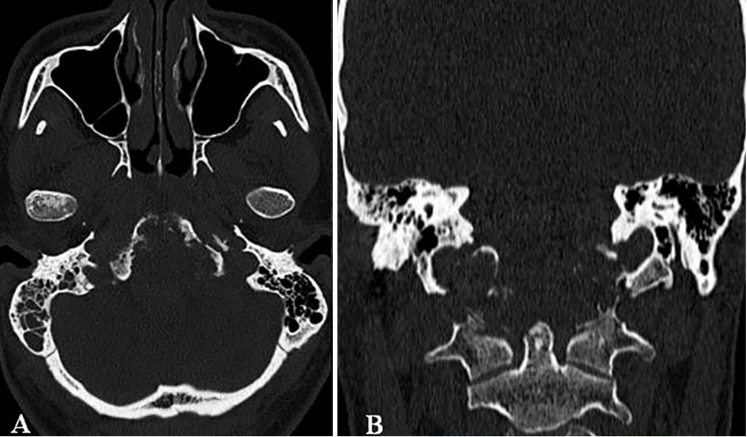

一名26岁男性患者,临床表现为颈部疼痛、严重吞咽障碍及双侧舌下神经麻痹(右侧完全性麻痹伴发舌肌萎缩,左侧为部分麻痹)。MRI与CT影像学检查结果显示,其颅颈交界区存在一直径达10厘米、体积约96.5立方厘米的巨大脊索瘤。该肿瘤呈浸润性生长,广泛侵犯右侧结构,累及范围包括椎前间隙、下斜坡、双侧枕骨髁、第一颈椎(C1)前弓以及第二颈椎(C2)齿状突。巨大肿瘤已导致脑干受压及双侧椎动脉移位,并向硬膜内扩张。

术前MRI与CT影像分别揭示了肿瘤的巨大范围及其对斜坡-枕骨髁造成的溶骨性破坏。主刀团队评估认为,肿瘤已对颅颈交界区骨质结构造成广泛侵蚀,术后极有可能出现颅颈不稳定。因此,手术方案确定为经远外侧经髁入路,施行显微镜与神经内镜双镜联合肿瘤切除术,继而进行枕颈融合术(OCF)。